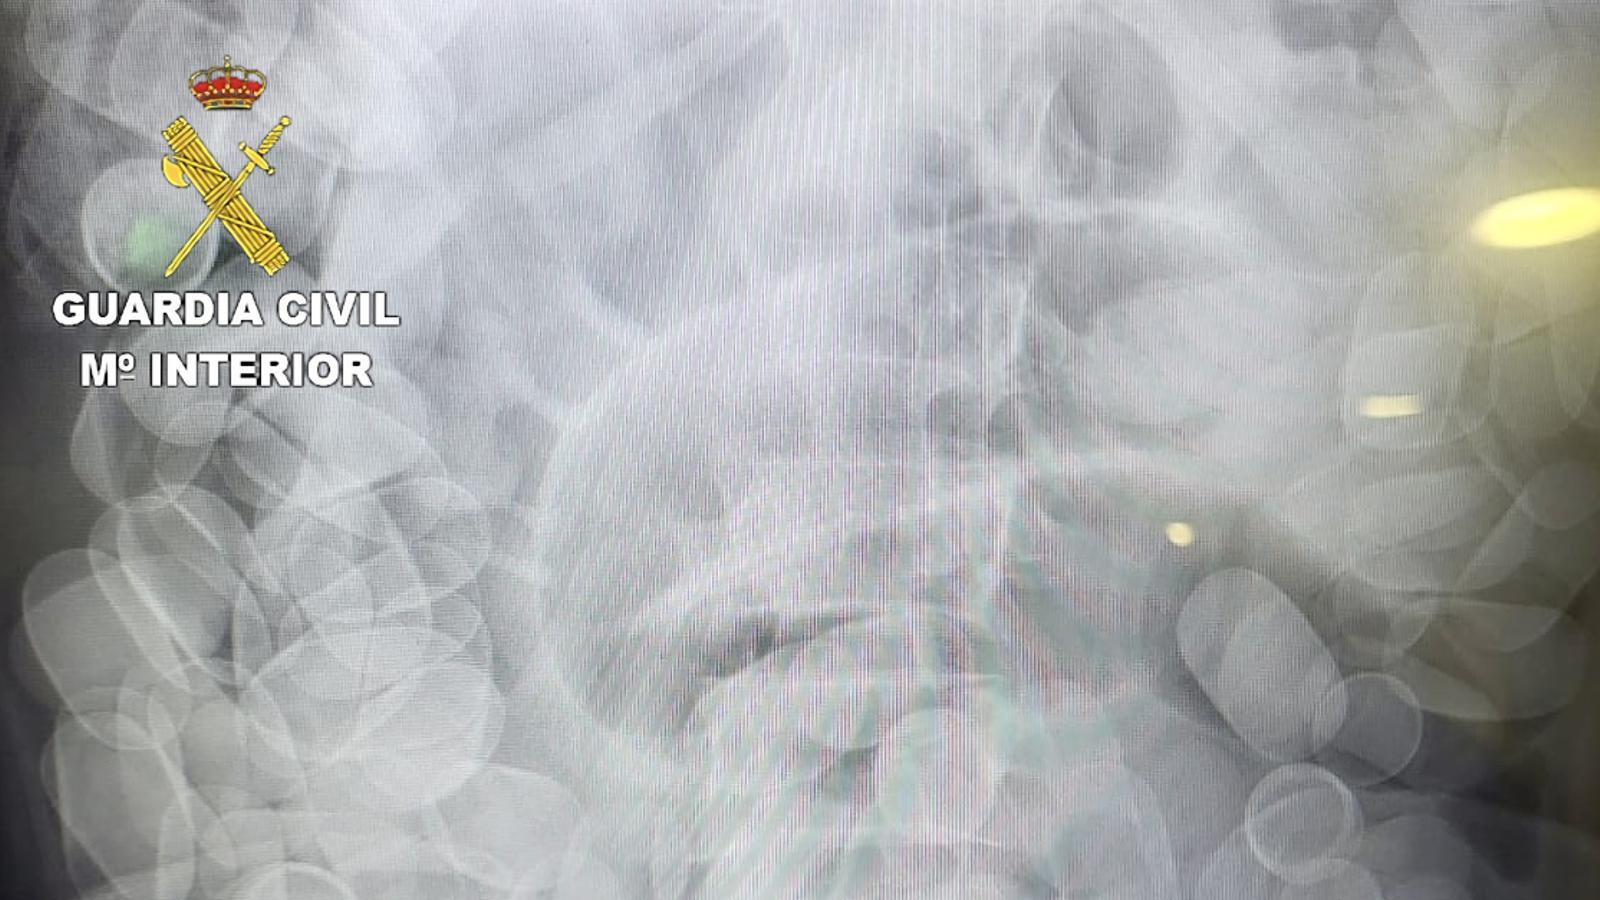

Radiografia on s'observen paquets de cocaïna ingerits

La Guàrdia Civil ha detingut a l’aeroport del Prat un passatger procedent de Sao Paulo (Brasil) que havia ingerit 1.480 grams de cocaïna en 153 cilindres. Segons informa el cos policial, la vida de l'home estava en perill perquè els paquets s'havien començat a trencar dins el seu organisme.

L'arrest va tenir lloc el 31 de juliol i es va produir perquè l'home actuava amb nerviosisme. Davant les sospites, el van fer passar per una prova de raigs X. El detingut va requerir una operació per treure-li la droga de l'organisme, i després de ser estabilitzat va ser traslladat al jutjat de guàrdia del Prat de Llobregat com a presumpte autor de delictes de tràfic de drogues i resistència i desobediència a l’autoritat.